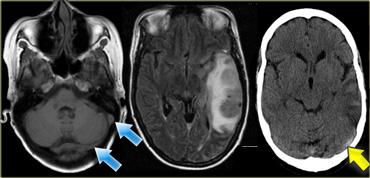

Hình CT bên trái cho thấy rõ hình ảnh xoang ngang bị huyết khối với tỷ trọng cao (mũi tên vàng).

Hình ảnh FLAIR cho thấy vùng nhồi máu tĩnh mạch ở thùy thái dương.

Bên trái là hình ảnh của một bệnh nhân bị huyết khối tĩnh mạch não sâu.

Lưu ý các vùng nhồi máu hai bên ở hạch nền.

Tiếp tục.

Không quan sát thấy khoảng trống dòng chảy (flow void) tại các tĩnh mạch não trong, xoang thẳng và xoang ngang phải (mũi tên xanh).

Trên hình MRA, xoang ngang phải không được hiển thị.